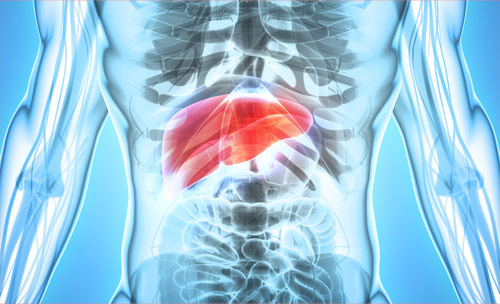

脾臓は赤血球を壊す・血小板を貯蔵する・抗体を作るなど様々な働きをしています。消化器系、栄養吸収不良や慢性疲労の改善、婦人科の疾患に関連が強いです。